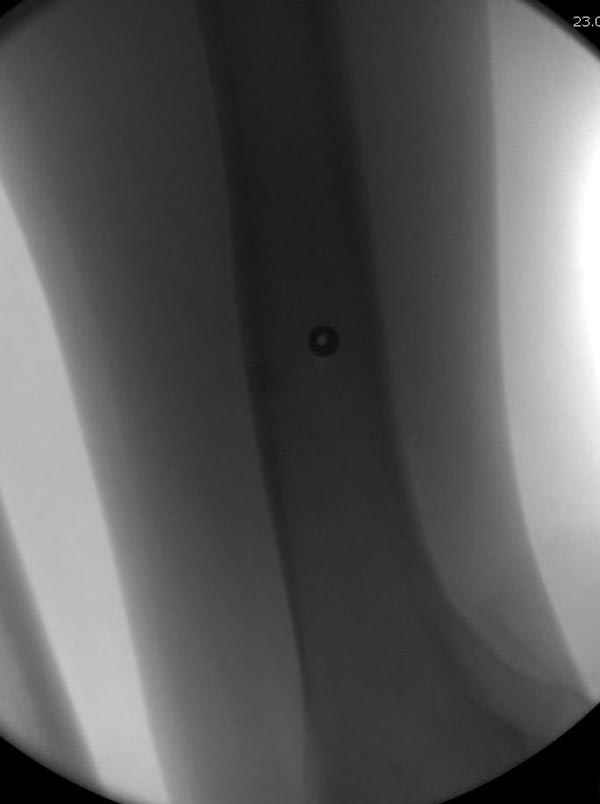

Методика штифтования при отсутствии большой зоны перелома как при онкологических профилактических штифтованиях, расверливание интрамедуллярного канала проводим с предварительным наложением дополнительного дренажного отверстия в дистальном отделе бедра (в данном случаи в канале оставили 6.5 мм канюлированный шуруп), иначе при создании давления в канале во время сверления имеется опасность эмболизации легочной артерии тромбом.

Ну, откатали методику на бомжике. Насветились под ЭОПом! Даже блокирующие шурупы поставили! Во что обошлась операция? А зачем тогда на форум выносить вопросы?

КД> Ну, откатали методику на бомжике. Насветились под ЭОПом! Даже

КД> блокирующие шурупы поставили! Во что обошлась операция?

Как было сказано, обошлось много дешевле, чем лечение весьма вероятных неприятностей в случае отказа от провизорной фиксации.